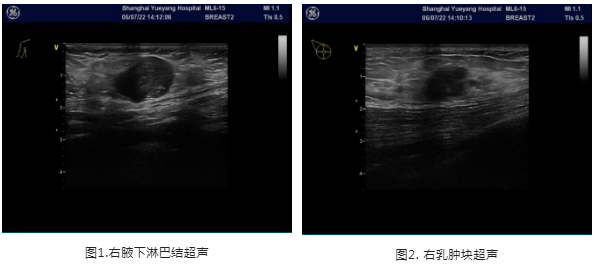

2021年6月8日乳房超声:右乳内见数个低回声区,较大者1点位20x10x18mm,边界欠清,形态欠规则,内见点状强回声,内见血流信号腋下:右侧见数个低回声区,较大者21x13mm,淋巴门结构不清晰,内见血流信号;

结论:右乳结节,BI-RADS 4B;右侧腋下淋巴结肿大

2022.06.07患者于我院行右乳肿块及右腋下肿大淋巴结空芯针穿刺活检术,穿刺病理病理:1.(右乳肿块穿刺)浸润性癌。2.(右侧腋窝淋巴结穿刺)见癌转移,首先考虑乳腺转移来源;